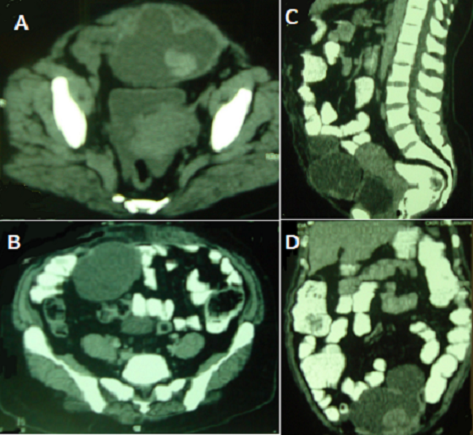

L'oubli d'un corps étranger textile est toujours possible au cours d'une chirurgie abdominale malgré les précautions draconiennes prises. La multiplicité et le manque de spécificité de ses présentations rendent son diagnostic difficile. Le meilleur traitement reste la prévention par le compte systématique des textiles et l'utilisation exclusive de compresses marquées, l'oubli d'une compresse étant toujours fautif. Nous rapportons le cas d'une patiente de 52 ans opérée il y a cinq ans pour une éventration ombilicale par la mise en place d'une prothèse qui présente une douleur abdominale à type de pesanteur évoluant depuis deux ans. A l'examen, on note une voussure sous-ombilicale de 15 x 10 cm. Le scanner abdomino-pelvien montre une masse pelvienne médiane pré-vésicale latéralisée à gauche mesurant 12 x 10 x 7,5 cm de densité hétérogène avec une large composante liquidienne et une composante périphérique spontanément hyperdense et quasiment non rehaussée par l'injection de produit de contraste. La masse prend corps avec les plans musculo-aponévrotiques notamment le muscle droit gauche évoquant une lésion tumorale musculaire primitive. Un kyste de l'ouraque dégénéré ou un hématome autours de la plaque décollée ont également été évoqués. La patiente a été opérée. Il existe une masse liquidienne intra-péritonéale de 15 cm de grand axe au contact du péritoine pariétal et reposant sur le dôme vésical. Il s'agit d'une cavité suppurée contenant la plaque qui est rétractée et un textilome (compresse). Il a été réalisé une évacuation du contenu de la cavité, une toilette et un drainage. Les suites opératoires étaient simples.